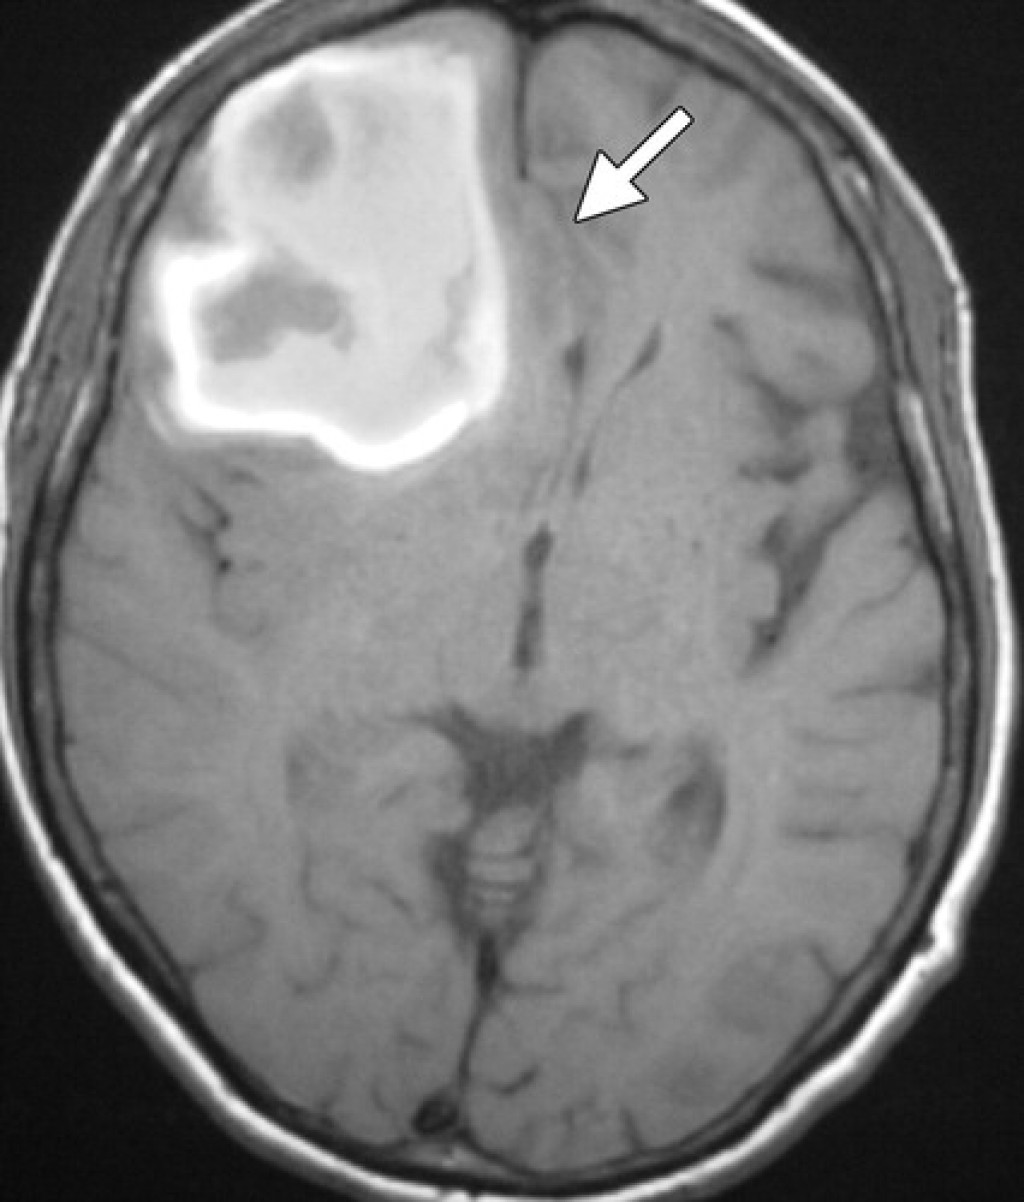

Внутричерепная гипотензия: КТ-исследования и их интерпретация

Раздел: Образы вокруг